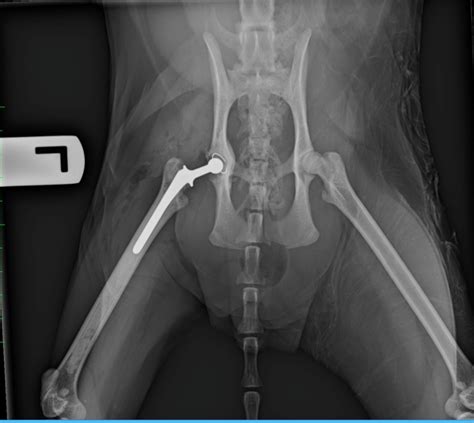

Larry Springer Blog